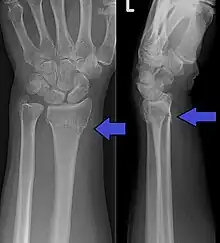

- (medicine) A distal fracture of the radius causing a dorsal displacement of the distal fragment, typically occurring as a result of a fall on an outstretched hand.